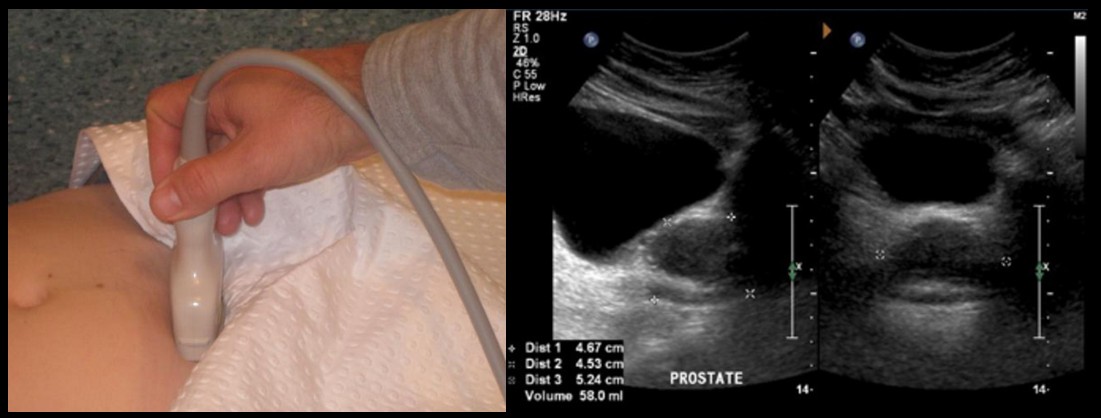

Los grados de crecimiento prostático (y observen que no hablamos de hiperplasia prostática) son definidos por la ecografía en relación al volumen de la glándula, divididos en 4 tipos:

Grado I, cuando la próstata tiene valores de 20 a 40 cc

Grado II; cuando la próstata se encuentra entre los 40 y 60 cc.

Grado III; cuando la próstata se encuentra entre los 60 y 80 cc.

Grado IV; cuando la próstata supera los 80 cc.

La intensidad y frecuencia de los síntomas prostáticos no siempre están directamente relacionados con el tipo de grado; dicho de otro modo; el hecho de tener una próstata de 80 cc no implica que un paciente tendrá síntomas más intensos y mas severos, o más complicaciones.